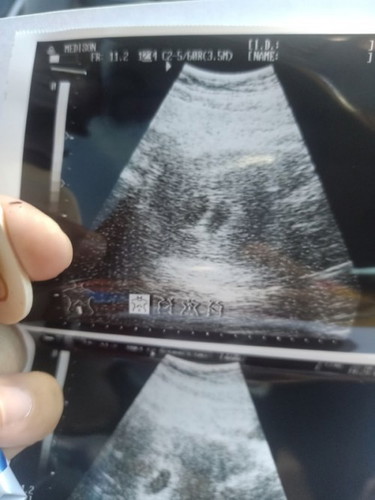

ไปอัลตร้าซาวด์มาเมื่อวานเหนถุงตั้งครรึ2ถุงแบบนี้เป็นไปได้ไหมค่ะที่จะมี2คน

เป็นไปได้จ้า